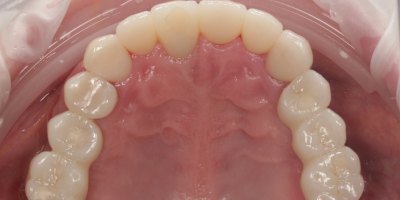

Была проведена имплантация: установлены импланты в области жевательных зубов нижней челюсти и в зоне переднего зуба верхней челюсти. После остеонтеграции имплантатов - проведено протезирование циркониевыми коронками.

Комплексное лечение позволило одновременно сохранить собственные зубы и восполнить отсутствующие участки с помощью имплантатов. Временные конструкции обеспечили адаптацию и комфорт сразу после операции. Постоянные циркониевые коронки восстановили гармонию улыбки, прочность и долговечность. В итоге пациент получил полноценный зубной ряд и красивую естественную улыбку.